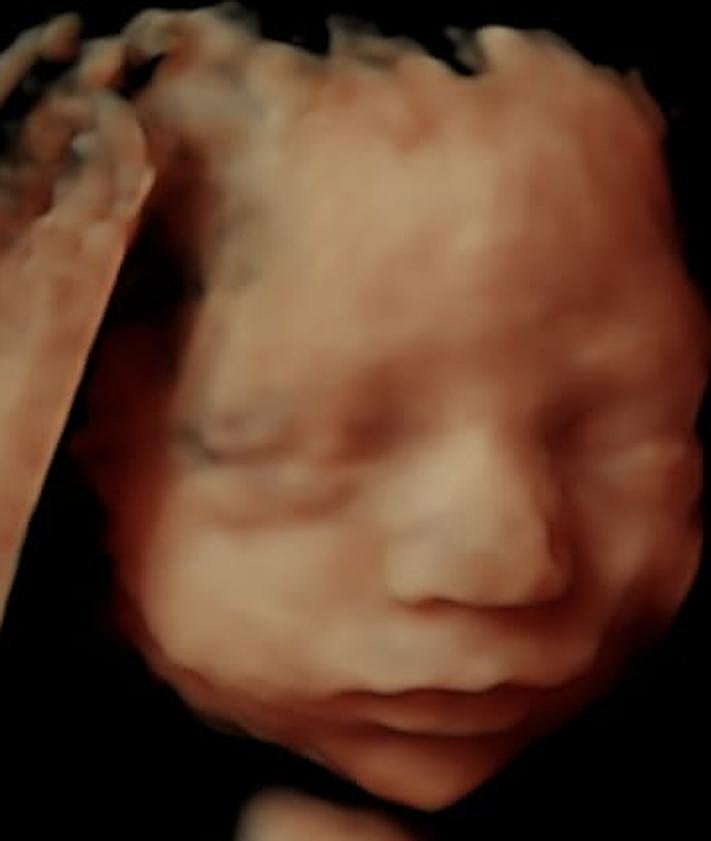

«El 5D es un paso más allá del 4D, mejora la iluminación y el sombreado. Por eso ya no utilizamos el 4D y pasamos del 3D directamente al 5D», detalla el propietario de NeoVida 5D. Todo esto les permite ofrecer servicios como «ecografías emocionales» que permiten a madres y padres a generar un vínculo de forma temprana con el bebé. Sin olvidar las ecografías en 8K, que utilizan la IA para, mediante una ecografía en 3D, hacer una fotografía hiperrrealista del bebé.

Sobre estas ecografías especiales, Eduardo aconseja esperarse a que avance el embarazo para que los resultados sean los mejores posibles. «Lo ideal es que las ecografías 5D se hagan entre las semanas 24 y 31, que es cuando mejor se va a ver al bebé», mientras que para el resto de etapas del embarazo aconseja recurrir a las 2D y 3D.